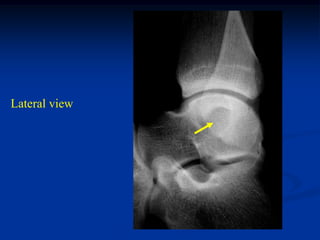

AP and lateral of right hip

AP and lat tibia

Proximal humeral x-rays

AP and lateral of femur

Lateral ankle

Oblique foot